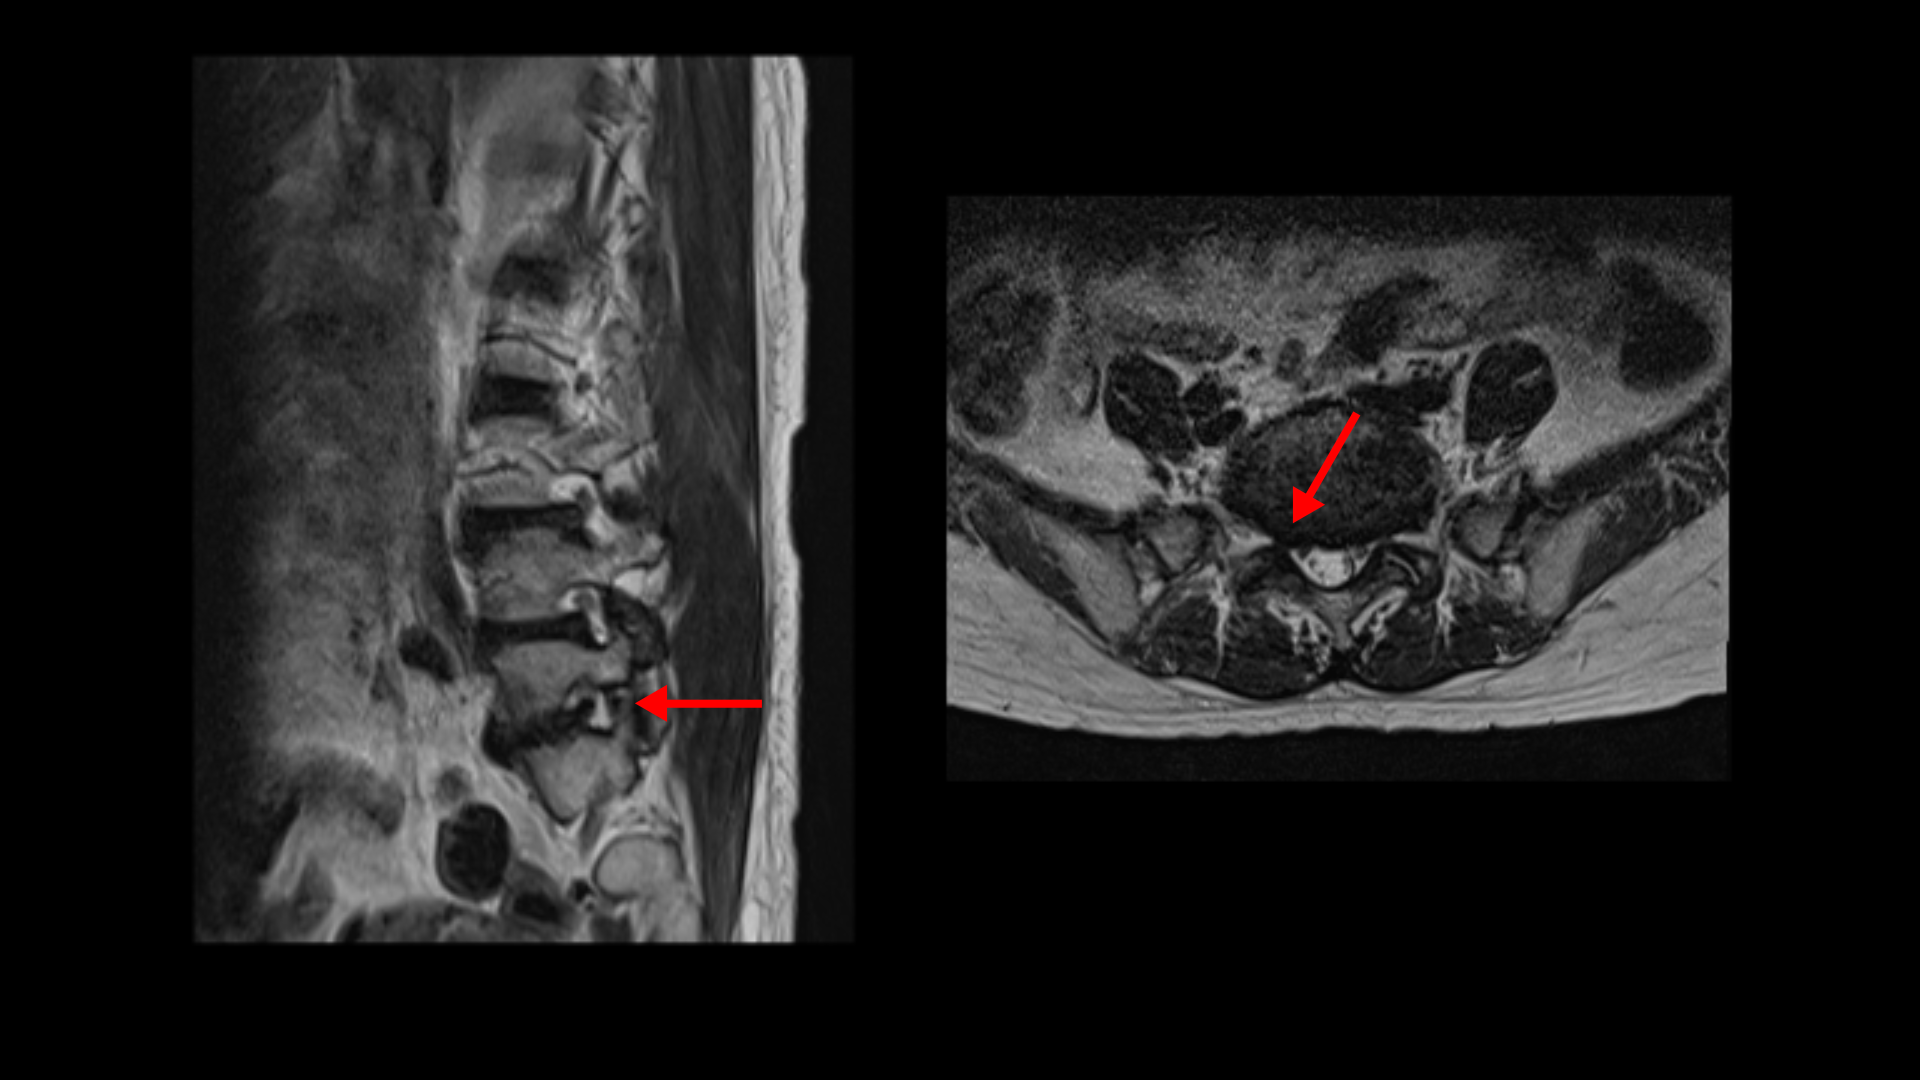

이분 MRI를 보면 3마디에 퇴행성디스크가 밀려 나와 있습니다.

또 3번 4번에는 척추전방전위증이 있습니다.

이 전방전위증 때문에 척추관에 중심성 협착도 있습니다.

4번 5번 디스크가 중앙에서 우측으로 약간 밀려 나와있고

>또 5번 1번에서는 신경이 빠져나가는 오른쪽 추간공이 약간 좁아져 있습니다.

이런 문제들 때문에 오른쪽 엉치부터 발가락까지 방사통이 있을 가능성이 있습니다. 하지만 어떤 마디가 정확한 통증의 원인인지 알기 어렵고 여러 마디가 안 좋기 때문에 이 환자분의 말씀을 들어봐도 전체적으로 여러마디 다 나사를 박자는 얘기를 들은 걸로 보입니다. 이렇게 여러 마디에 나사를 박는 유합술을 해놓으면 시간이 흘러 위나 아래에 문제가 생길 가능성도 커지고 환자분도 50대 초반의 젊은 나이라 대학병원의 교수님도 수술하기엔 너무 젊은 데라고 여러 번 말씀하셨다고 합니다. 그런데 신경 주사를 그토록 여러 번 오랜 시간 맞았는데도 환자가 심하게 아프면 수술 외에는 뾰족한 다른 방법이 없는 것이죠.

그런데 이분 허리 MRI를 자세히 보면 딱히 신경이 아주 극심하게 눌린 곳도 없습니다.

신경이 조금 눌릴 수는 있어도 심각해 보이지는 않습니다.

신경구멍이 지나가는 길이 여러 가지 퇴행성 변화로 조금씩은 좁아져 있지만 굳이 수술로 특히 여러 마디의 나사를 박는 수술까지 해가며 신경압박을 해소해야 할 정도의 심한 신경눌림은 보이지 않는 겁니다.